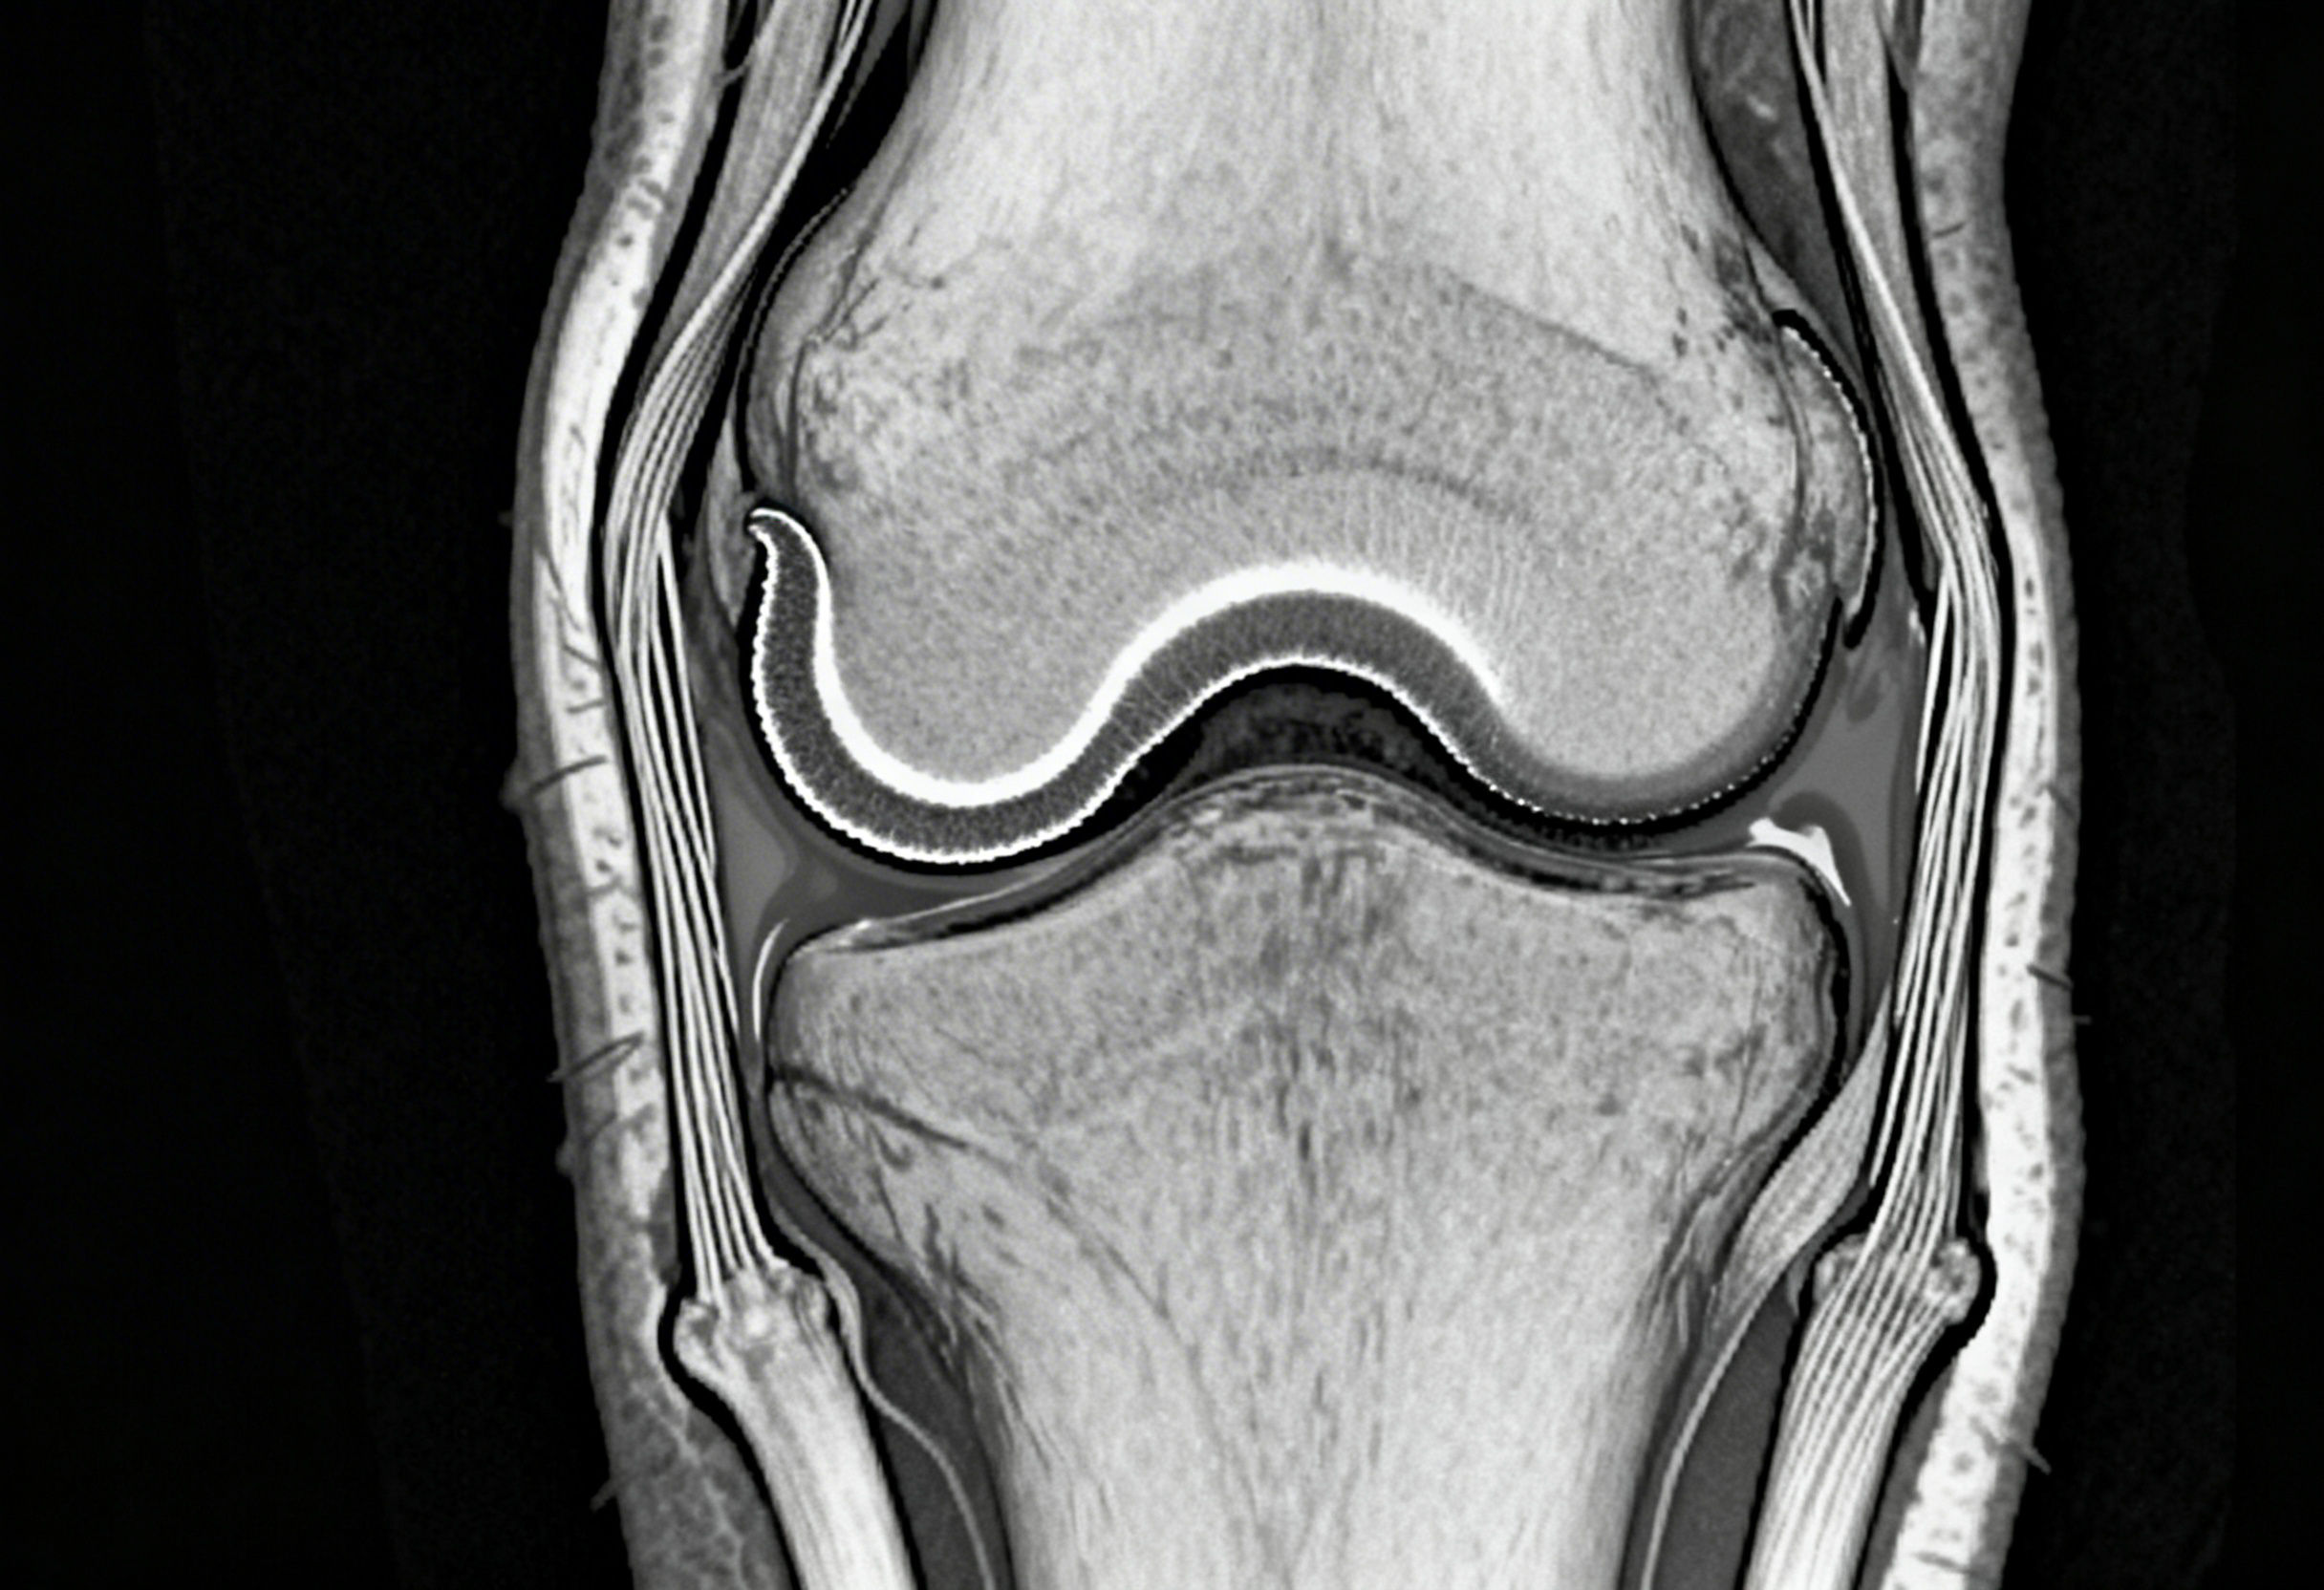

Understanding Knee Ligament Injuries Beyond MRI Reports

Knee ligament injuries are one of the most common causes of chronic knee pain, instability, and early-onset osteoarthritis. Many patients are told they have a “normal MRI” or a “minor sprain,” yet continue to experience giving way, deep joint pain, swelling after activity, or fear of movement. This disconnect happens because knee pain is often driven by ligament laxity, not complete ligament rupture.

Even a few millimeters of elongation can disrupt normal biomechanics. This instability often does not show clearly on static imaging such as MRI, which is taken without load or movement. Clinical examination frequently reveals instability that imaging misses.